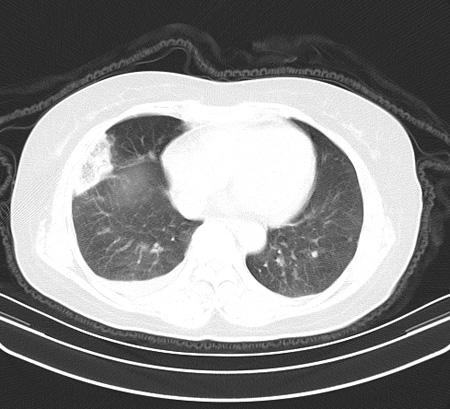

以下是引用余辉在2009-2-19 20:10:00的发言:[br]多考虑急性感染性病变,右中叶尚可见多枚小斑片状影,多为化脓性肺炎,双侧胸腔积液

以下是引用随光逐影在2009-2-19 20:33:00的发言:[br]1)考虑右肺炎症;建议抗炎治疗后复查。2)双侧胸腔积液(以右侧为甚)。

以下是引用花凤凰在2009-2-19 20:46:00的发言:[br]病人有发热,胸痛急性起病,主要病变位于右肺中叶外侧段,呈楔行改变,位于外带胸膜下,考虑为肺梗塞可能!!!!!!!!!!!!!!!!!!!!!!!!!!!!!!!!!!!